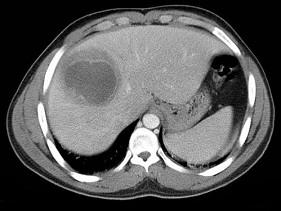

下列图像的最佳诊断是 ( )A.阿米巴肝脓肿B.原发性肝癌C.肝硬化D.脂肪肝E.肝囊肿

问题 下列图像的最佳诊断是 ( )

选项 A.阿米巴肝脓肿 B.原发性肝癌 C.肝硬化 D.脂肪肝 E.肝囊肿

答案 A